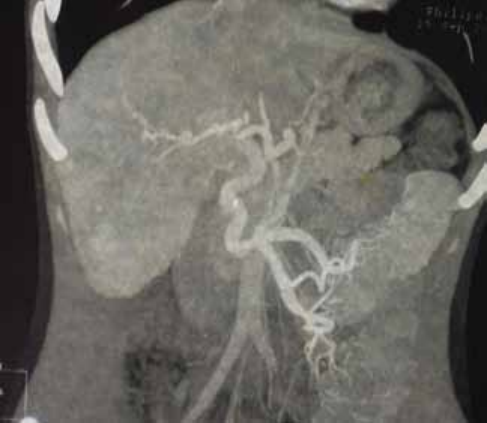

Благоприятный исход операции проксимального СРВШ демонстрируем на клиническом примере пациентки Л. 22 лет с циррозом печени вирусной этиологии, варикозным расширением вен пищевода и желудка III ст. (в анамнезе эпизод кровотечения), печёночно-клеточной недостаточностью класса А (4 балла по Child-Turcotte-Pugh) спустя 7 лет после операции (рис. 2). Анализ результатов и эффективности лечения установил отсутствие рецидивов кровотечения, редукцию варикозного расширения вен пищевода, полную резорбцию асцита, энцефалопатии.

Рисунок 2. Спиральная компьютерная томограмма пациентки Л., 29 л., через 7 лет после операции спленоренального венозного шунтирования. КТ признаки множественных сосудистых анастомозов вокруг головки поджелудочной железы с ветвями брыжеечной вены и левой почечной веной, расширение яичниковой вены

Figure 2. Spiral computed tomography of patient L., 29 years old, 7 years after splenorenal venous bypass surgery. CT scan shows signs of multiple vascular anastomoses around the head of the pancreas with branches of the mesenteric vein and the left renal vein, dilation of the ovarian vein